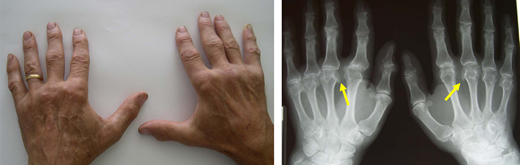

The index patient had a 62-year-old brother living in a rural area whose test results indicated C282Y homozygosity. His biochemical profile showed ferritin level, 1020 mg/L; TSAT, 78%; and a mild elevation of transaminases. Two years before, he had received a diagnosis of seronegative undifferentiated arthritis with poor response to hydroxychloroquine. A physical examination and plain radiogram showed typical hemochromatosis arthropathy of the hands (Figure 5). The Fib-4 score and FibroScan confirmed the high probability of ALF,25 making a liver biopsy unnecessary. There were no clinical or biochemical signs of other relevant complications. Phlebotomy, surveillance for HCC, and physiotherapy of involved joints were started.

Hemochromatosis arthropathy. Typical bilateral involvement of the metacarpophalangeal joints, especially the second and third, with plain radiogram showing the classical “hook” osteophytes. Hemochromatosis arthropathy can involve multiple other joints, including the hip, ankle, knee, elbow, shoulder, and spine.